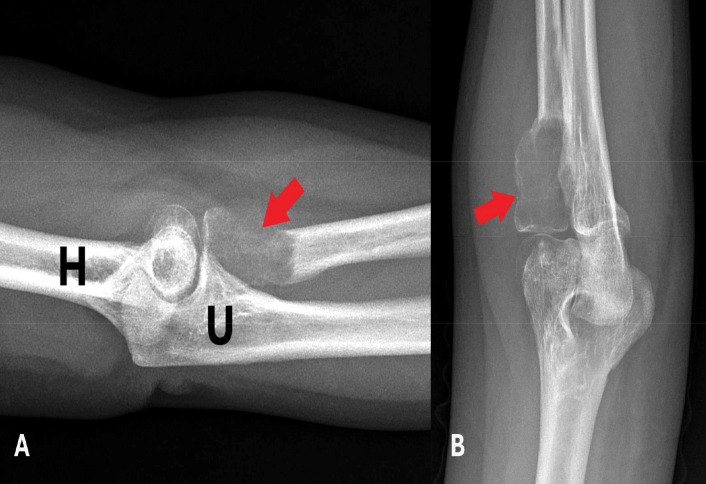

30岁男性左肘疼痛肿胀。多模态放射学评估显示一个扩张性溶解性骨病变,伴有液体-液体水平和周围软组织水肿,局限于桡骨头。组织学检查证实了动脉瘤性骨囊肿(SVABC)的实变,这是一种解剖学上罕见的病变。病变经过刮除处理,导致完全的临床解决。教学要点:结合影像学和组织学发现,准确诊断和有效治疗SVABC,特别是当发生在非典型部位时,它们可能模仿更侵袭性的肿瘤。

A 30-year-old male presented with pain and swelling in the left elbow. Multimodal radiologic evaluation revealed an expansile, lytic bone lesion with fluid-fluid levels and surrounding soft tissue edema, localized in the radial head. Histological examination confirmed the diagnosis of a solid variant of aneurysmal bone cyst (SVABC), an anatomically rare site for such lesions. The lesion was managed with curettage, leading to complete clinical resolution. Teaching point: integrating radiologic and histologic findings to an accurate diagnosis and effective management of SVABC, especially when occurring in atypical locations where they may mimic more aggressive neoplasms.